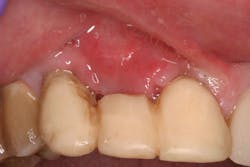

- Antiseptic mouthrinse. StellaLife has been shown to assist in tissue healing and prevent possible infections in areas of open wounds in multiple case series (figures 3–9).1